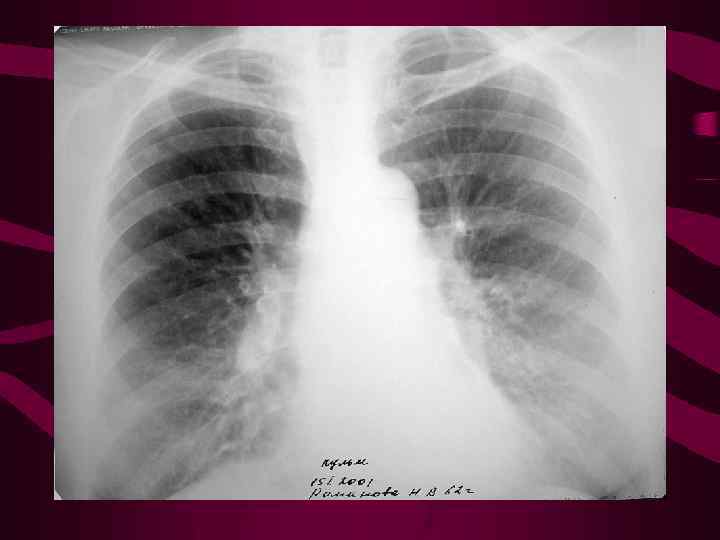

Схема перераспределения легочного кровотока при левожелудочковой недостаточности ↑ давления в ЛП и венулах от 25 до 35 мм рт. ст. повышенная трассудация плазмы в интерстициальные ткани Несоответствие между объемом фильтрации плазмы из капиляров и скоростью ее отведения скопление жидкости в междольковых перегородках, междолевых щелях, плевральной полости 3 ст. - интерстициальный отек

Схема перераспределения легочного кровотока при левожелудочковой недостаточности ↑ давления в ЛП и венулах от 25 до 35 мм рт. ст. повышенная трассудация плазмы в интерстициальные ткани Несоответствие между объемом фильтрации плазмы из капиляров и скоростью ее отведения скопление жидкости в междольковых перегородках, междолевых щелях, плевральной полости 3 ст. - интерстициальный отек

3 - интерстициальн ый отек легких Среднее давление в левом предсердии от 25 до 35 мм рт. ст. На фоне диффузного венозного застоя выявляются признаки нарушения лимфооттока из легких. Прозрачность легочных полей понижена. Легочный рисунок усилен, полиморфный, наблюдается ячеистая его деформация с нечеткостью контуров сосудов и бронхов. Выявляются линии Керли, Выпот в плевральную полость и междолевые щели, чаще справа.

3 - интерстициальн ый отек легких Среднее давление в левом предсердии от 25 до 35 мм рт. ст. На фоне диффузного венозного застоя выявляются признаки нарушения лимфооттока из легких. Прозрачность легочных полей понижена. Легочный рисунок усилен, полиморфный, наблюдается ячеистая его деформация с нечеткостью контуров сосудов и бронхов. Выявляются линии Керли, Выпот в плевральную полость и междолевые щели, чаще справа.